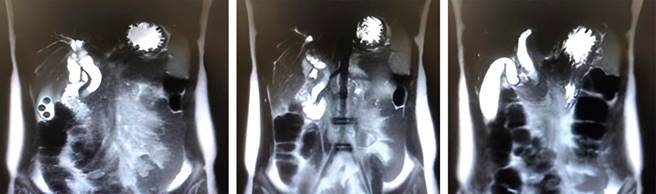

Dos días después, el paciente mostró aumento de su tinte íctérico en mucosas y piel y persistencia de dolor en hipocondrio derecho. Una nueva CRM reveló distención vesicular importante (diámetro longitudinal de 88 mm) con presencia de dos cálculos de 8 mm, el colédoco con aumento de su diámetro proximal (calibre máximo 13 mm), y disminución de su lumen distal (porción intramural), con una imagen hipointensa (5 mm) que podría corresponder a cálculo neumobilia, además de dilatación de la vía intrahepática (Figura 1).

Figura 1: Vesícula biliar con distensión con diámetro longitudinal de 88 mm, en su interior con al menos dos cálculos de 8 mm. Aumento de diámetro proximal y disminución del lumen a nivel distal del conducto colédoco; dilatación de la vía intra y extrahepática, con calibre máximo del colédoco de 13 mm. Se observa a nivel distal del colédoco (porción intramural) pequeña imagen hipointensa de 5 mm que podría corresponder a cálculo distal o neumobilia.